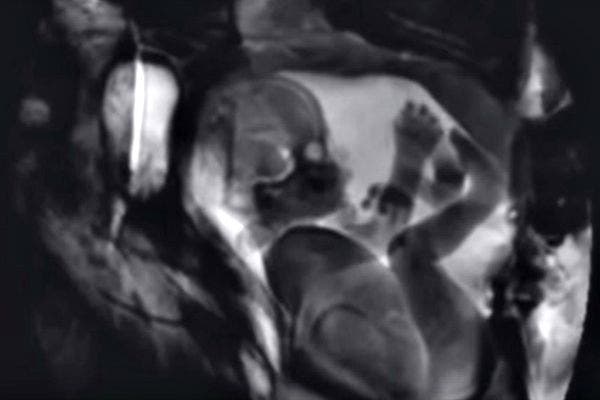

4. When a man and a woman love each other, they sometimes make a baby.

The MRI machine also captured a baby in utero. It's pretty amazing how much detail you can see on the baby — fingers, toes, eyes, and brain.